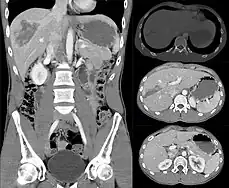

Imaging, such as the use of ultrasound or a computed tomography scan, is the generally preferred way of diagnosis as it is more accurate and is sensitive to bleeding, however; due to logistics this is not always possible.[6] For a person who is hemodynamically unstable a focused assessment with sonography for trauma (FAST) scan may take place which is used to find free floating fluid in the right upper quadrant and left lower quadrant of the abdomen. The FAST scan however may not be indicated in those who are obese and those with subcutaneous emphysema.[7] Its speed and sensitivity to injuries resulting in 400mL of free-floating fluid make it a valuable tool in the evaluation of unstable persons. Computed tomography is another diagnostic study which can be performed, but typically is only used in those who are hemodynamically stable.[7] A physical examination may be used but is typically inaccurate in blunt trauma, unlike in penetrating trauma where the trajectory the projectile took can be followed digitally.[8] A diagnostic peritoneal lavage (DPL) may also be utilized but has limited application as it is hard to determine the origin of the bleeding.[9] A diagnostic peritoneal lavage is generally discouraged when FAST is available as it is invasive and non-specific.[7]